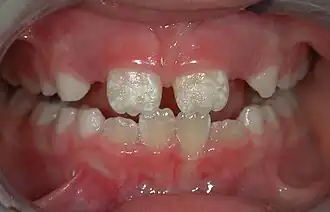

The normal color of enamel varies from light yellow to grayish (bluish) white. It has been suggested that the color is determined by differences in the translucency of enamel, yellowish teeth having a thin, translucent enamel through which the yellow color of the dentin is visible and grayish teeth having a more opaque enamel. The translucency may be attributable to variations in the degree of calcification and homogeneity of the enamel. At the edges of teeth where there is no dentin underlying the enamel, the color sometimes has a slightly blue or translucent off-white tone, easily observable on the upper incisors. Since enamel is semitranslucent, the color of dentin and any material underneath the enamel strongly affects the appearance of a tooth. The enamel on primary teeth has a more opaque crystalline form and thus appears whiter than on permanent teeth.

Some groups have spoken out against fluoridated drinking water, for reasons such as the neurotoxicity of fluoride or the damage fluoride can do as fluorosis. Fluorosis is a condition resulting from the overexposure to fluoride, especially between the ages of 6 months and 5 years, and appears as mottled enamel.[3] Consequently, the teeth look unsightly, although the incidence of dental decay in those teeth is very small. Where fluoride is found naturally in high concentrations, filters are often used to decrease the amount of fluoride in water. For this reason, codes have been developed by dental professionals to limit the amount of fluoride a person should take.[38] These codes are supported by the American Dental Association and the American Academy of Pediatric Dentistry.

There are 14 different types of amelogenesis imperfecta.[3] The hypocalcification type, which is the most common, is an autosomal dominant condition that results in enamel that is not completely mineralized.[53] Consequently, enamel easily flakes off the teeth, which appear yellow because of the revealed dentin. The hypoplastic type is X-linked and results in normal enamel that appears in too little quantity, having the same effect as the most common type.[53]

Enamel hypoplasia is broadly defined to encompass all deviations from normal enamel in its various degrees of absence.[55] The missing enamel could be localized, forming a small pit, or it could be completely absent.